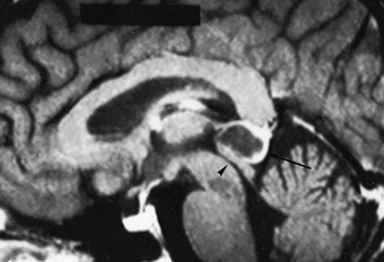

Among central nervous system (CNS) tumors, the widest variety of pathologic types occurs in the region of the pineal gland and posterior third ventricle . The numerous cell types that make up the normal gland and surrounding periventricular region contribute to these diverse histologic subtypes. The pineal gland is composed of glandular tissue, glia, endothelial cells, and sympathetic nerve terminals. Pineal cell tumors and pineoblastomas arise from pineal glandular elements, astrocytomas and oligodendrogliomas from glial cells, hemangioblastomas from endothelial cells, and chemodectomas from sympathetic nerve cells. Arachnoid cells in the reflections of the tela choroidea adjacent to the pineal gland give rise to meningiomas. Ependymomas arise from ependymal cells that line the third ventricle. Germ cell tumors (GCTs) derive from primitive germ cell rests that are retained in the pineal and other midline structures after embryologic migration courses. Pineal tumors account for approximately 1% of all intracranial tumors in the United States. In Asia, where GCTs are endemic, pineal cell tumors constitute 4% to 7% of all intracranial tumors.

PINEAL CELL TUMORS

Pineal cell tumors arise from pineocytes and range from histologically primitive pineoblastomas to well-differentiated pineocytomas. Attempts to correlate prognosis and survival with either variant have been inconclusive because both may behave in a malignant fashion, with recurring at the primary site and spreading through the CSF. Pineal cell tumors occur in children and young adults before age 40 with no sex predominance. They are occasionally found concurrently with retinoblastomas and may contain mixed cell types. The pineoblastomas are considered a variant of primitive neuroectodermal tumors. Pineal cell tumors are radiosensitive, but experience with chemotherapy is limited.